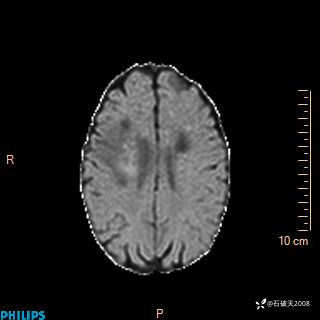

2020.11.14MR

FLAIR